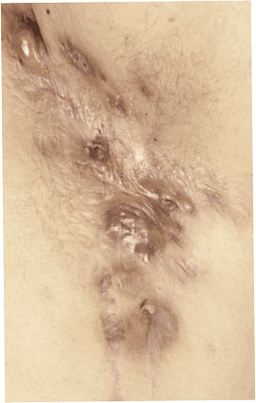

Hidradenitis suppurativa (HS)

Hidradenitis suppurativa (HS) är en kronisk hudsjukdom med smärtsamma knölar. Orsaker inkluderar ärftlighet, könshormoner, övervikt och rökning.